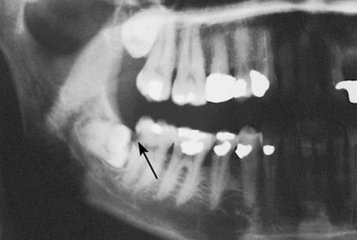

智齒拔牙比較複雜,而且難度大,所以不少患者不敢拔牙,或者是擔心拔智齒會(hui) 有危險。深圳牙科醫生表示,其實一般正規的醫院拔智齒是非常安全,可以放心的,而且一般情況下拔牙後醫生都會(hui) 詳細告知拔牙後注意事項。...

智齒拔牙比較複雜,而且難度大,所以不少不敢拔牙,或者是擔心拔智齒會(hui) 有危險。深圳牙科醫生表示,其實一般正規的醫院拔智齒是**,可以放心的,而且一般情況下拔牙後醫生都會(hui) 詳細告知拔牙後注意事項,不會(hui) 有危險的。